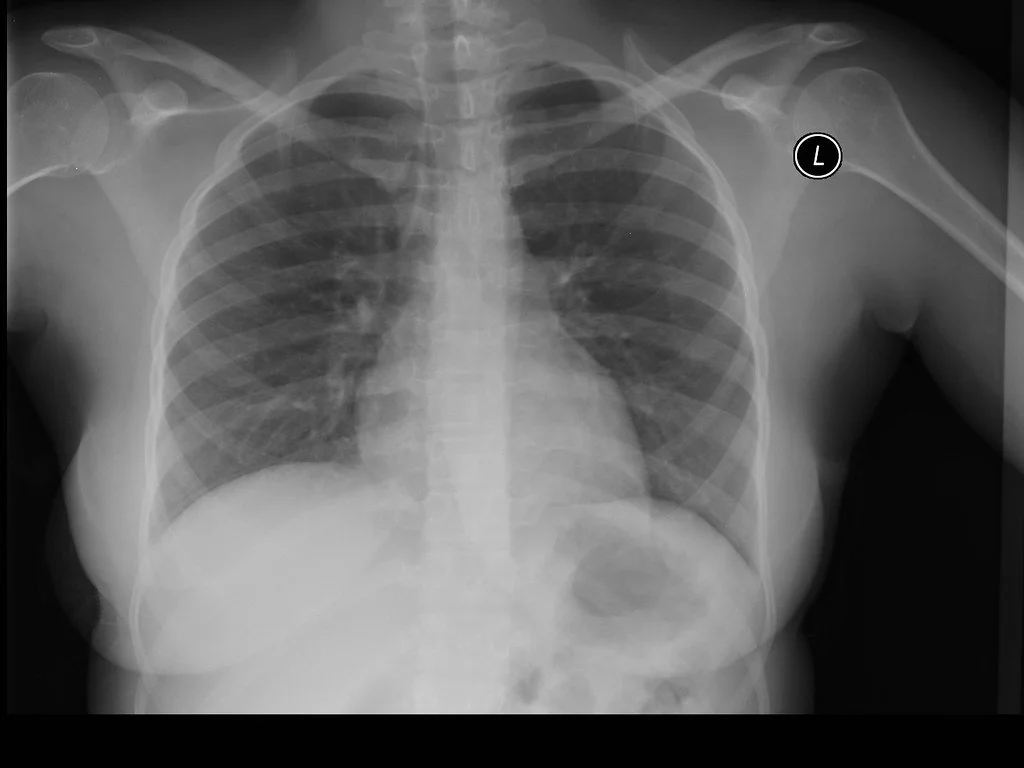

Read MoreChest imaging is a cornerstone of emergency and acute care decision-making, but its value depends on using the right modality at the right time. This post explores a practical approach to chest X-ray, ultrasound, and CT, highlighting indications, limitations, and common diagnostic pitfalls. Designed for clinicians working in fast-paced, high-risk environments.